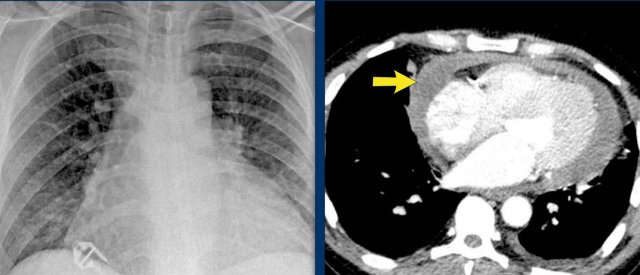

Pericardial effusion

When encountering an enlarged cardiac silhouette on chest radiography, it is essential to consider pericardial effusion as a potential mimic of cardiomegaly.

Case Example 1: Pericardial Effusion Mimicking Cardiomegaly

- On the chest radiograph, the patient appears to have a dilated heart.

- However, CT imaging clearly demonstrates that the apparent enlargement is due to significant pericardial fluid accumulation, not true myocardial chamber enlargement.

Case Example 3: Valve Replacement & Heart Failure

Post-valve replacement, a patient presents with a markedly enlarged cardiac silhouette on chest X-ray.

Findings

- A large cardiac silhouette

- There is evidence of pulmonary vascular redistribution, suggesting congestive heart failure.

Case Example 3: CT imaging

CT demonstrates a large pericardial effusion.

Tip

Always compare postoperative chest films with preoperative imaging to detect interval changes such as effusions or evolving heart failure.